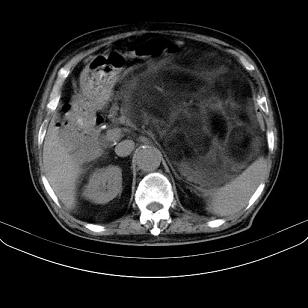

标题: CT21671:男,88岁,左上腹包块 [打印本页]

标题: CT21671:男,88岁,左上腹包块

患者因咳嗽而住院,自觉右上腹包块,无其他不适。

腹膜后高分化脂肪肉瘤

腹膜后脂肪肉瘤

腹膜生占位性病变,脂肪肉瘤可能。

左侧腹膜后脂肪肉瘤。